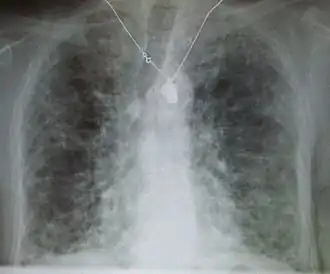

Pneumocystis pneumonia can present with interstitial lung disease, as seen in the reticular markings on this AP chest x-ray.

A chest x-ray is 63% sensitive and 93% specific for ILD.[10] With advances in computed tomography, CT scans of the chest have supplanted lung biopsy as the preferred diagnostic test for ILD. A thoracic CT scan is 91% sensitive and 71% specific for ILD.[10] In higher income countries, less than 10% of people with ILD undergo a lung biopsy as part of the diagnostic evaluation.[16]